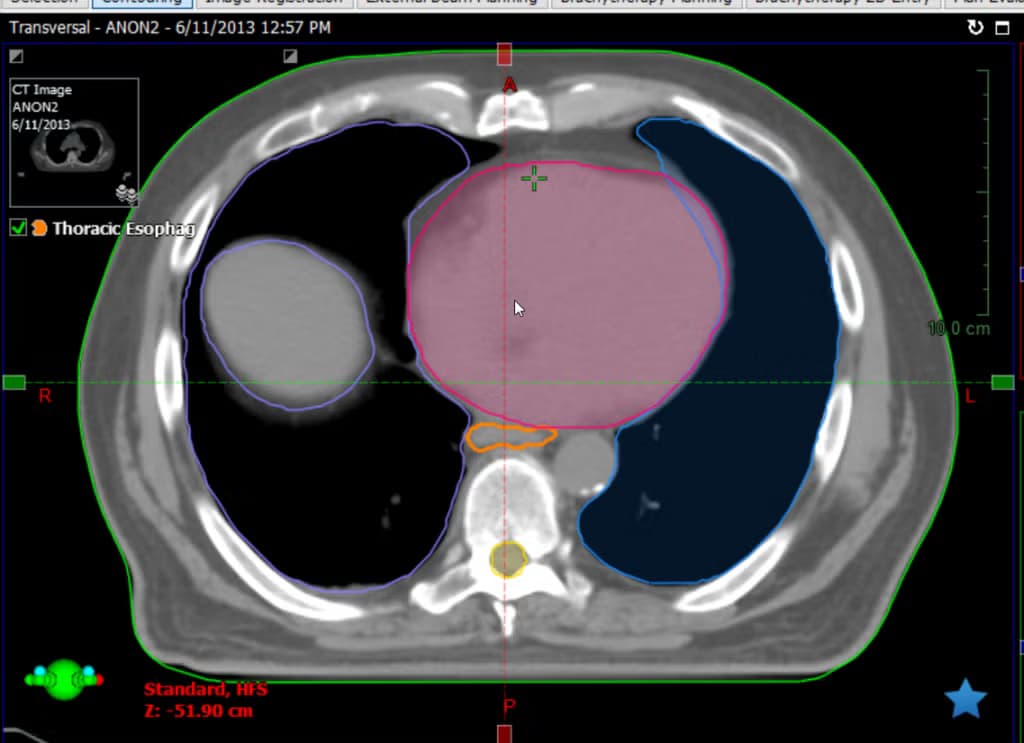

From Prototype to FDA Clearance

How Quantiva transformed Penn Medicine's AI research prototype into an FDA-cleared commercial platform for radiation oncology treatment planning.